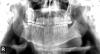

qehreman Опубликовано 7 октября, 2010 Поделиться Опубликовано 7 октября, 2010 Какую аномалию вы видите в нижней чельюсти? Ссылка на комментарий

hogsmeed Опубликовано 7 октября, 2010 Поделиться Опубликовано 7 октября, 2010 Какую аномалию вы видите в нижней чельюсти?Ну у вас девятка периодонтитная Ссылка на комментарий

Kivilgar Опубликовано 7 октября, 2010 Поделиться Опубликовано 7 октября, 2010 Какую аномалию вы видите в нижней чельюсти?А там не перелом? Ссылка на комментарий

zybnaya feya Опубликовано 7 октября, 2010 Поделиться Опубликовано 7 октября, 2010 А там не перелом?+1 к периодонтитной девятке и перелому Ссылка на комментарий

Kilgen Опубликовано 8 октября, 2010 Поделиться Опубликовано 8 октября, 2010 согласен с переломом... Ссылка на комментарий

barakuda73 Опубликовано 9 октября, 2010 Поделиться Опубликовано 9 октября, 2010 Pt 4.9, + вероятен перелом Ссылка на комментарий

qehreman Опубликовано 9 октября, 2010 Автор Поделиться Опубликовано 9 октября, 2010 Pt 4.9, + вероятен переломперелом челюсти??? Вы простите, загадку загадываете? Ситуацию и жалобы при осмотре опишите? Ему туда мышьяк выставили потом врач вдруг заявил что не собирается лечить его. Теперь у него челюсть полностью не открывается и когда силой открывает рот, челюсть свисает (постепенно в сторону) Ссылка на комментарий

Aldo Rain Опубликовано 10 октября, 2010 Поделиться Опубликовано 10 октября, 2010 нет тут перелома, глотка наслаиваеца Ссылка на комментарий

Aldo Rain Опубликовано 11 октября, 2010 Поделиться Опубликовано 11 октября, 2010 V smisle?А что не понятно? Кто-то предположил перелом челюсти,я говорю что его нет Ссылка на комментарий